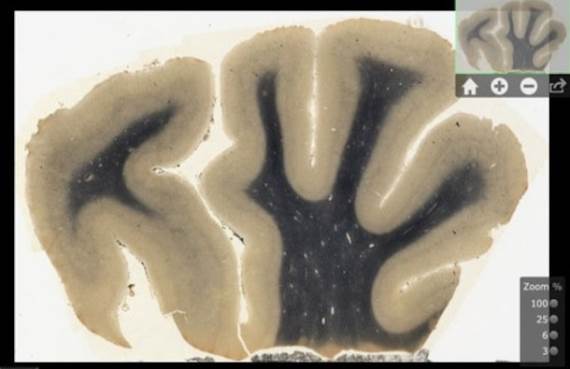

Predstavljena je posebna aplikacija za iPad tablet uređaj, koja bi trebalo da naučnicima učini dostupnijim detaljne snimke mozga Alberta Ajnštajna.

Medicinski muzej, u formiranju u Čikagu, dobio je sredstva za skeniranje i digitalizaciju oko 350 slajdova s prikazima delova Ajnštajnovog mozga nakon njegove smrti 1955. godine i to je iskorišćeno za pravljenje ove aplikacije.

Ona će omogućiti istraživačima i inovatorima da prodru u ekscentričan mozak dobitnika Nobelove nagrade kao da gledaju kroz mikroskop, nebi li eventualno saznali šta je to što je Ajnštajnu omogućilo genijalnost i naučne uspehe.